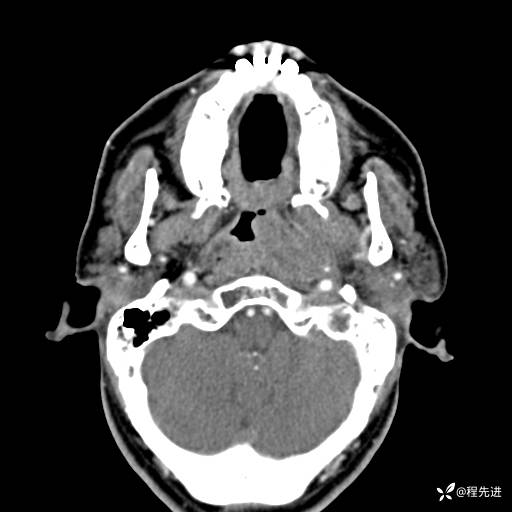

CT平扫:

CT增强:

动脉期: